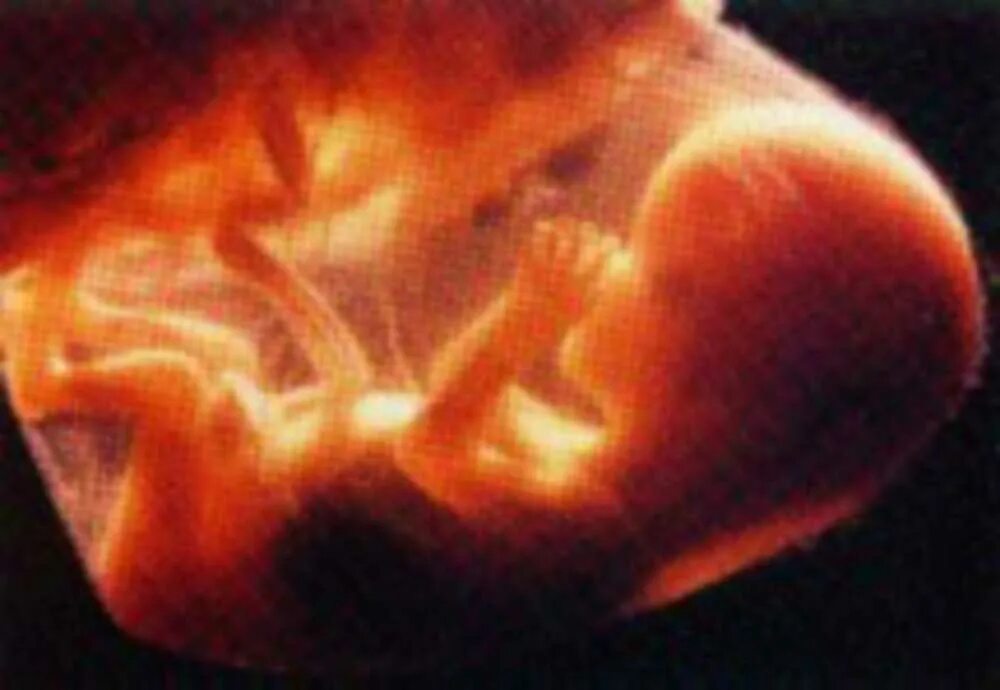

19 недель фото плода